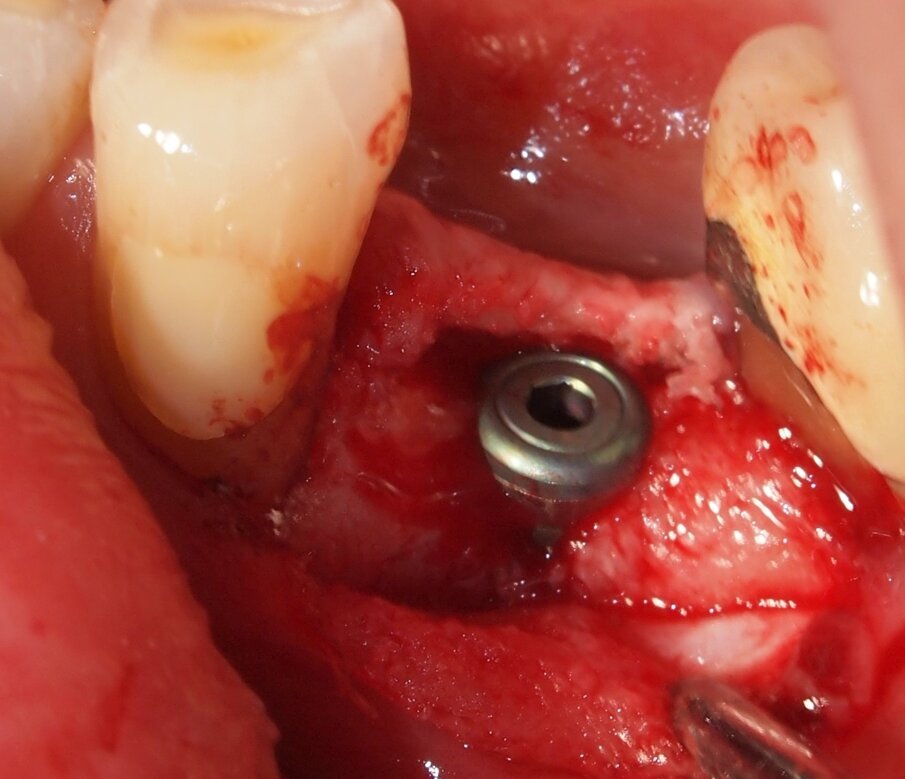

Fig. 6 - Caso clinico 1. Sollevamento di un lembo mucoperiosteo ed esposizione della corticale ossea. Si apprezza macroscopicamente l’assenza di fenomeni di carbonizzazione e danni termici dei tessuti molli e del tessuto osseo che mantiene un’adeguata vascolarizzazione.

Fig. 7 - Caso clinico 1. Posizionamento di una fixture di dimensioni adeguate al caso clinico in esame.